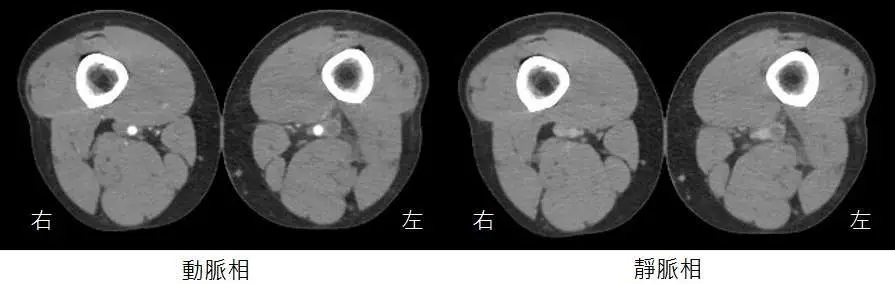

35歲男性病人,主訴持續一星期的單側下肢腫脹,但無發燒症狀。雙側下肢靜脈注射顯影劑電腦斷層影像如圖所示,下列關於病況的敘述何者最恰當? 圖片描述

– 左圖為動脈相(arterial phase),僅動脈內顯影劑充填良好,靜脈內尚未完全顯影。

– 右圖為靜脈相(venous phase),對照正常對側可見靜脈完全顯影;疑似病灶側(左側)股靜脈區段缺乏顯影劑充填,形成「空洞狀」腔內充填缺損,此為靜脈內血栓(acute DVT)的典型表現,且該側靜脈較對側腫大,提示靜脈淤積與急性水腫(ajronline.org)。

影像中為左側股靜脈出現充填缺損,代表病灶側為左下肢;右側靜脈顯影正常,故本選項錯誤。